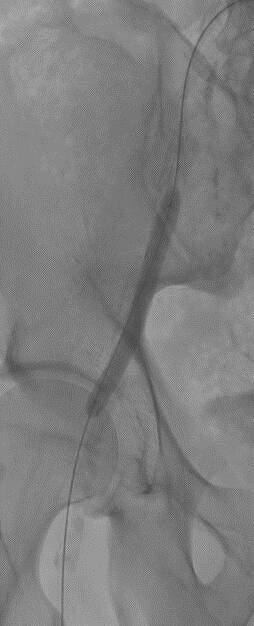

Via een prik in de lies wordt een buisje in je slagader geplaatst. Via deze toegang kunnen we jouw slagader volledig en zeer nauwkeurig in beeld brengen. Indien er vernauwingen of verstoppingen vastgesteld worden, kunnen deze dan in dezelfde tijd behandeld worden. Ter hoogte van de vernauwing wordt een ballon opgeblazen. Indien blijkt dat dit onvoldoende is kan aanvullend een stent in uw bloedvat geplaats worden. Vermits er enkel een prik in de lies nodig is, hoef je slechts 1 nacht in het ziekenhuis te blijven. Thuis mag je snel zo goed als al uw activiteiten hernemen